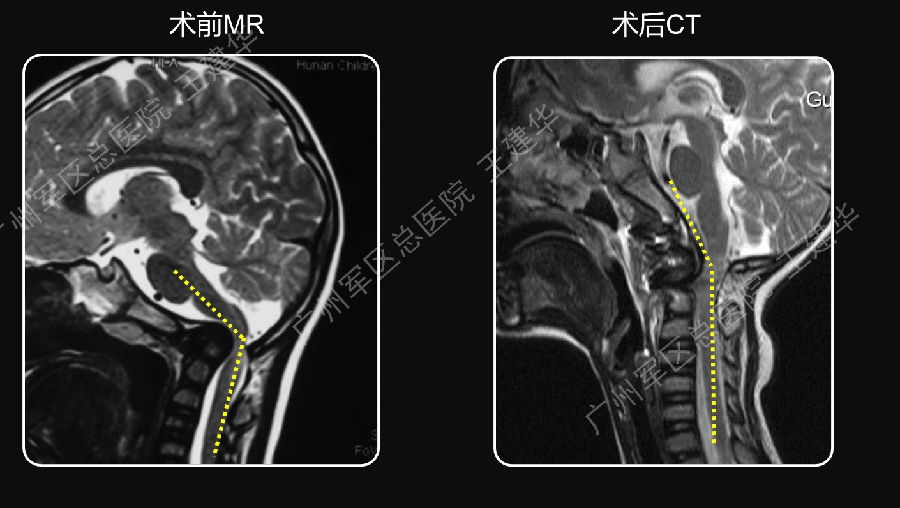

颈椎MR检查提示:颈椎上端结构陷入枕骨大孔,脑干受压变形

手术前后对比

可以看到:

陷入枕骨大孔的寰椎和齿突已经下拉复位,枕颈排列恢复正常

脑干压迫解除,延髓脊髓角恢复正常

手术后6年复查:

颅颈椎序列恢复正常并骨性融合